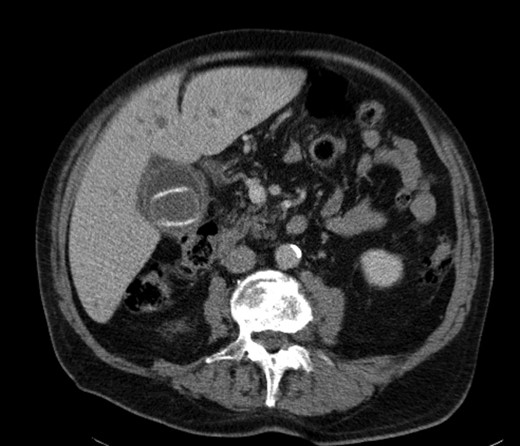

A 92-year male, with no significant co-morbidities apart from peptic ulcers, was admitted with 6 days of obstination. On examination he was dehydrated, with a hugely distended abdomen but no signs of peritonitis. Blood showed features of dehydration and plain abdominal X-ray demonstrated both small and large bowel dilatation, but no obvious causal pathology. A contrast-enhanced computed tomography scan revealed a 2.5-cm partially calcified gallstone impacted at the descending colon-sigmoid junction (Fig. 1). There was no stricture or diverticular disease distal to the stone. A cholecysto-colic fistula could be seen (Fig. 2), with a further smaller gallstone in the caecum (Fig. 3). The offending gallstone could be seen incidentally in the gallbladder on imaging 3 years previously (Fig. 4).

CT reconstruction showing the impacted gallstone and a smaller incidental gallstone in the caecum.